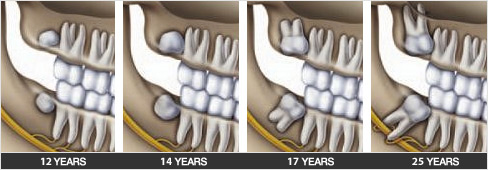

The normally wisdom teeth appear between 17 and 25 years of age

Also known as wisdom teeth, they are the last teeth to appear. Anthropologists have noted that the abrasive diet of men in the beginning of history caused excessive wear on their teeth. The displacement of the worn teeth allowed for the wisdom teeth to grow.

Today, as a result of a more refined diet and orthodontic treatments, our teeth occupy all the available space and leave little room for growth of the third molars. There is only partial growth or inclusion of the wisdom tooth which could eventually cause problems.

Extraction of the third molars is generally easier in young patients because they are not fully formed and the bone around the teeth is more pliable. In addition, there is less risk of damaging surrounding structures such as the nerves, the maxillary sinus and adjacent teeth. Extractions can be more complex at a later age. Root development may involve the nerve that gives feeling to the chin and lip. The jaw is denser and the extraction is more complex.